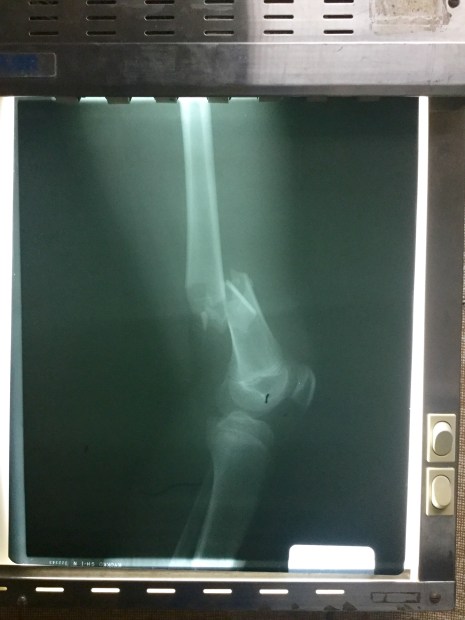

The above X-ray shows a gunshot wound that is passing through this young man’s knee, his femur. On the left, you can see the cylindrical outline of the bullet’s trajectory. He told us that there was just ‘a lost bullet’ that found it’s way into his knee. It’s really weird how it’s angled down, from the inside of his knee slightly outward. Kind of like he had it tucked in the front of his pants and accidentally shot himself… Whoopsies!